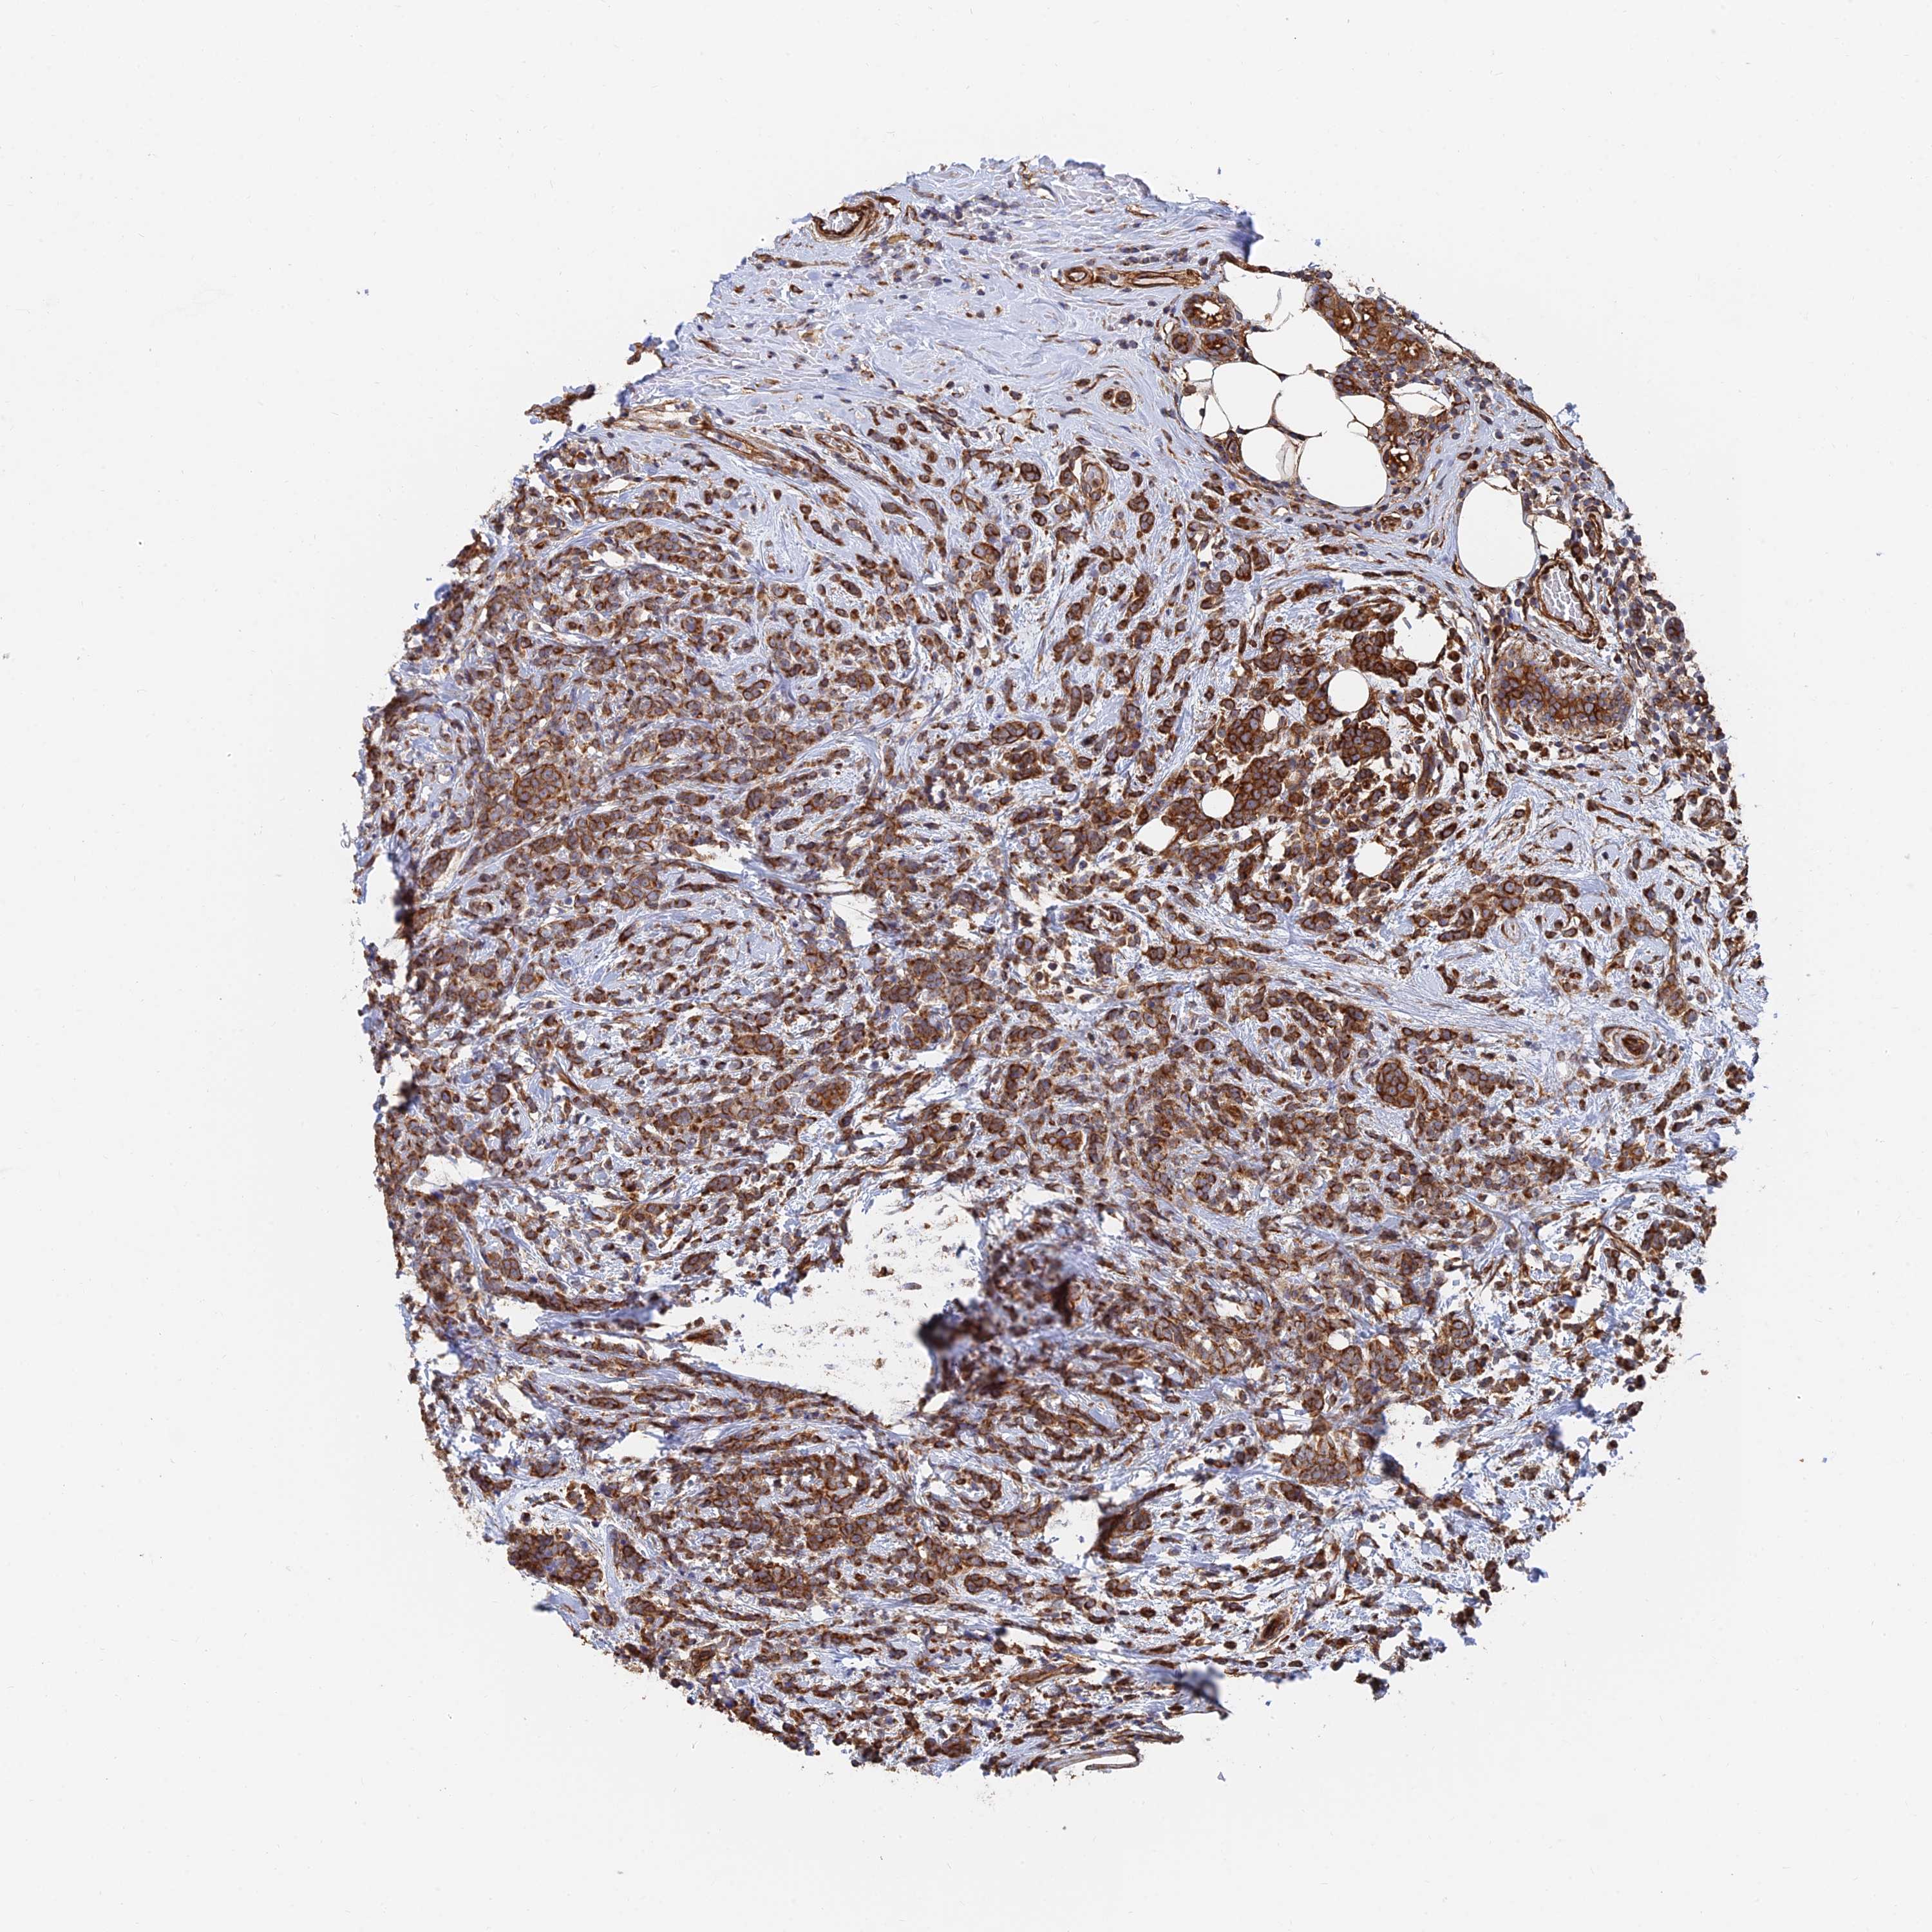

BRCA TCGA BRCA VALIDATION PROTEIN EXPRESSION

ANTIBODIES

AND

VALIDATION